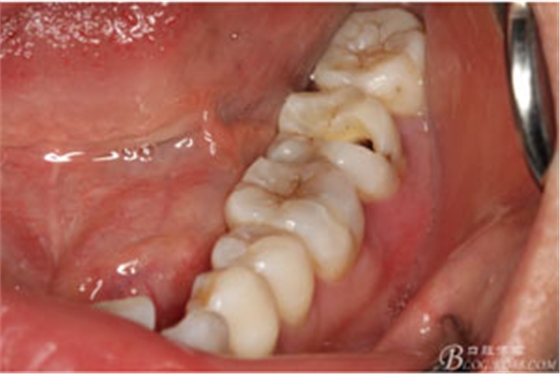

圖3.取出棉球口內(nèi)發(fā)現(xiàn)37合面有開髓孔,探針出血,頰側(cè)牙齦紅腫